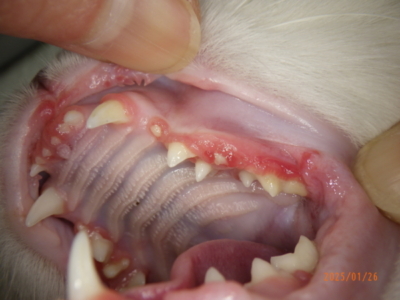

当院にて初診時、お口を確認するとまず、歯肉が赤くモリモリしていることがわかります。そして、奥の方は赤く腫れていないので、幸い口内炎にはなっていないようです(口内炎は喉のほうまで赤く腫れます)。歯は確かに本数は多いのですが、乳歯にしてはそれぞれの歯がしっかりしています。これらのことから、若齢猫の歯肉増殖症と、過剰歯の存在と推測しました。これらの病態の説明は後述しますが、いずれにしろ肉眼のみでの検査では診断も難しいため、全身麻酔下での歯科レントゲンを用いた精査、また歯肉の盛り上がった部位は一部採取して病理検査に提出することにしました。

当日の肉眼写真です。

上顎

下顎

左右上顎と、右下顎の歯は明らかに歯の生え方に異常がありました。